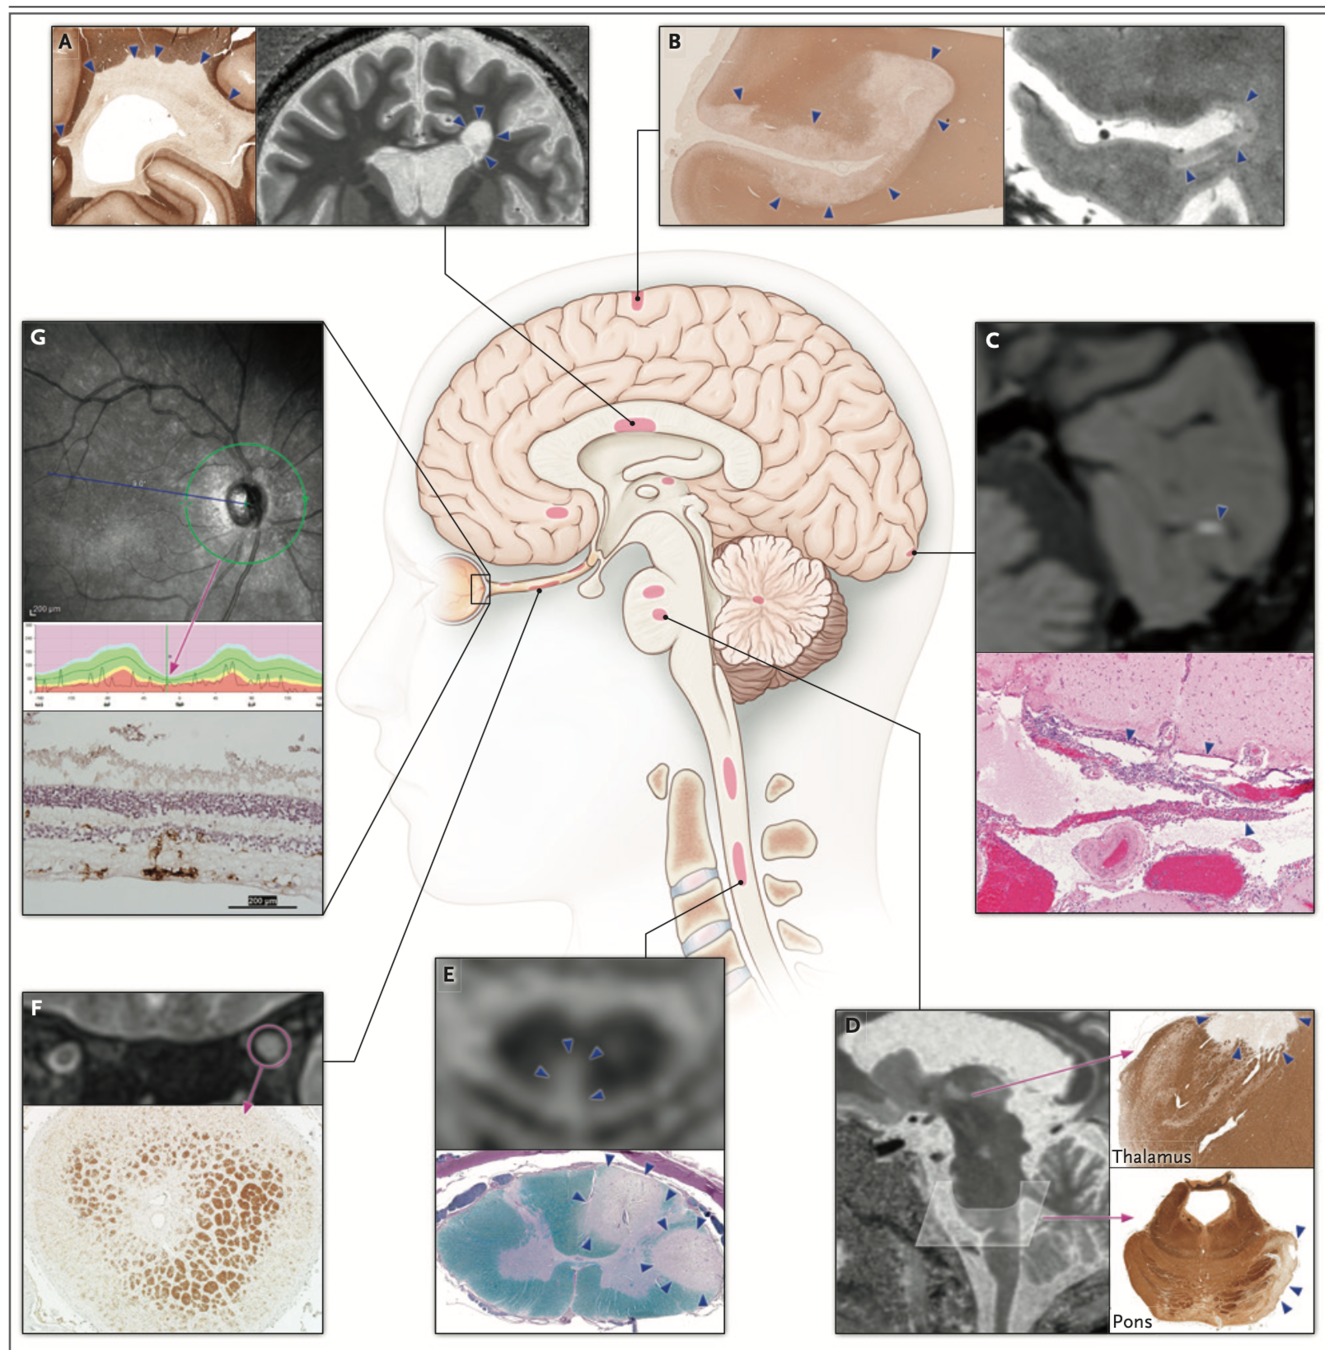

Exames de Imagem

incluir as imagens e as caracteristicas de em